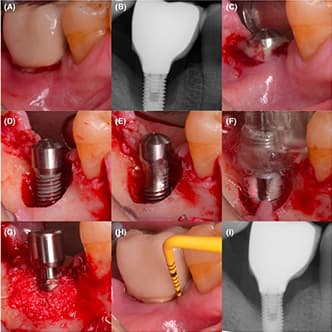

Bone Growth in Inflammatory Condition: Peri-implantitis Clinical Trial

A prospective, double-blind randomized clinical trial evaluated PEMF therapy for peri-implantitis in patients with dental implants and crowns. Treatment with Magdent’s MED device resulted in a notable reduction in marginal bone loss after one month. This improvement remained stable during a three-month follow-up.